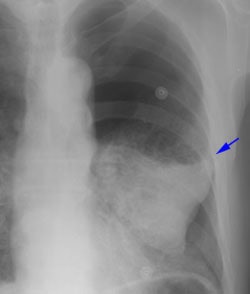

Example 2: This patient is an example of a false negative CT for hilar nodal metastases even when applying the suggested new criterion. The patient had a peripheral adenocarcinoma in the left upper lobe (black arrows). The left hilar node (yellow arrows) is not pathologic by size criteria, nor does it exhibit a convex margin with the adjacent lung parenchyma. This is a normal node by CT, however, at histopathologic analysis the node was positive for malignant cells.

NOTE: Click image to enlarge